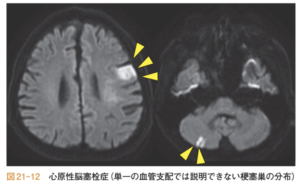

| MRI | ①心原性か非心原性か![]() ②どの領域か(ACA?MCA?PCA?) ![]() |

| 画像 | 皮質領域を含む梗塞巣を呈することが特徴![]() |